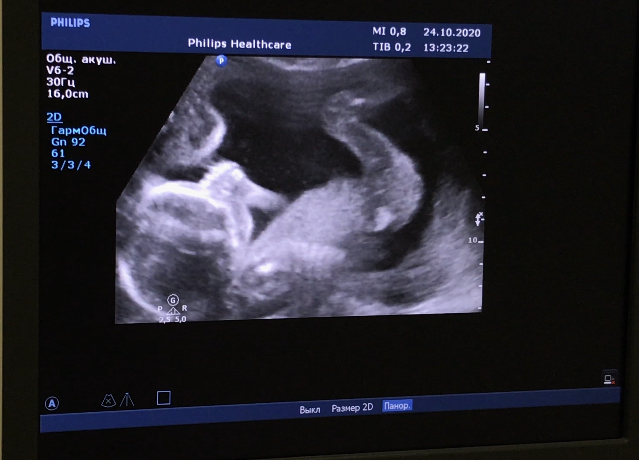

Всем привет!❤️ На фото нам почти 19 неделек. Сосем пальчик и бултыхаемся от души вниз головой))

По скринингу у нас все хорошо, все на месте. Сказали, будем высокими, родимся под 60см даже возможно😅